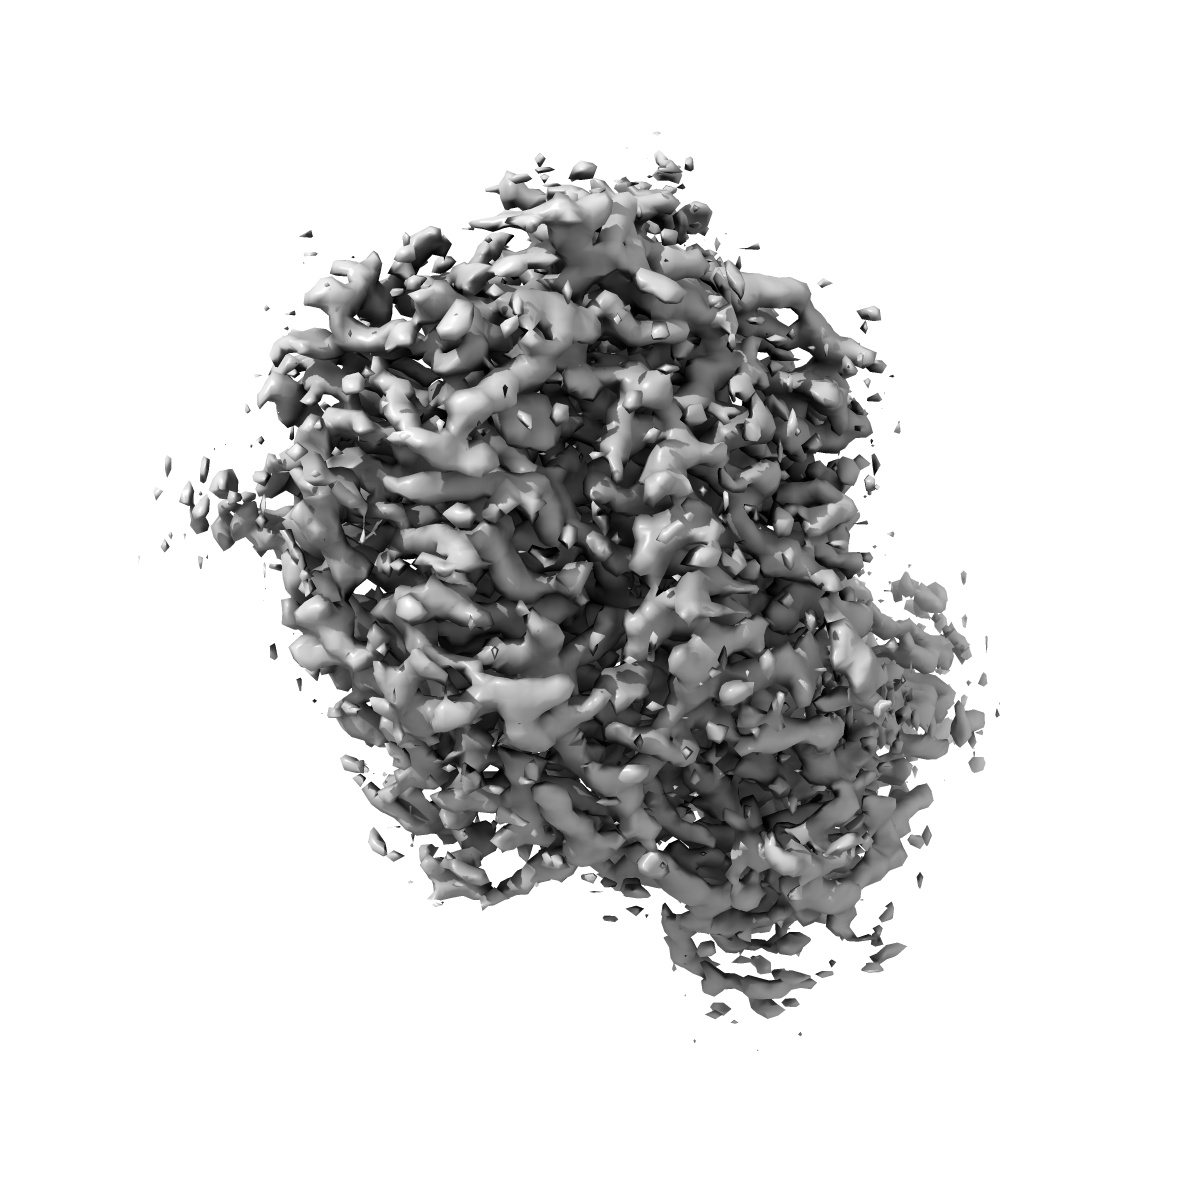

Cryo-EM structure of SARS-CoV2 RBD-ACE2 complex

EMD-30816

Single-particle

2.8 Å

Sample Organism: Homo sapiens, Severe acute respiratory syndrome coronavirus 2

Sample: Cryo-EM structure of SARS-CoV2 RBD-ACE2 complex

Fitted models: 7dqa

Deposition Authors: Wang J, Lan J

Reduced graphene oxide membrane as supporting film for high-resolution cryo-EM

Liu N, Zheng LM, Xu J, Wang J, Hu CX, Lan J, Zhang X, Zhang JC, Xu K, Cheng H, Yang Z, Gao X, Wang XQ, Peng HL, Chen YN, Wang HW

(2022) Biophys Rep , 7 , 227 - 238

DOI: doi:10.52601/bpr.2021.210007